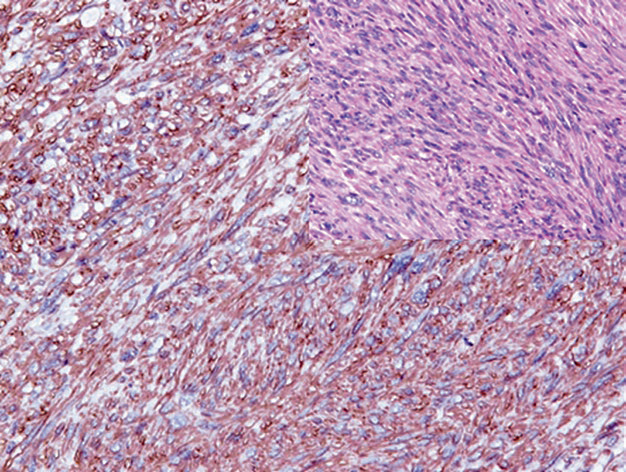

Figure 1. Pleomorphic rhabdomyosarcoma, immunohistochemistry shows significant expression of desmin in the cytoplasm of tumor cells.